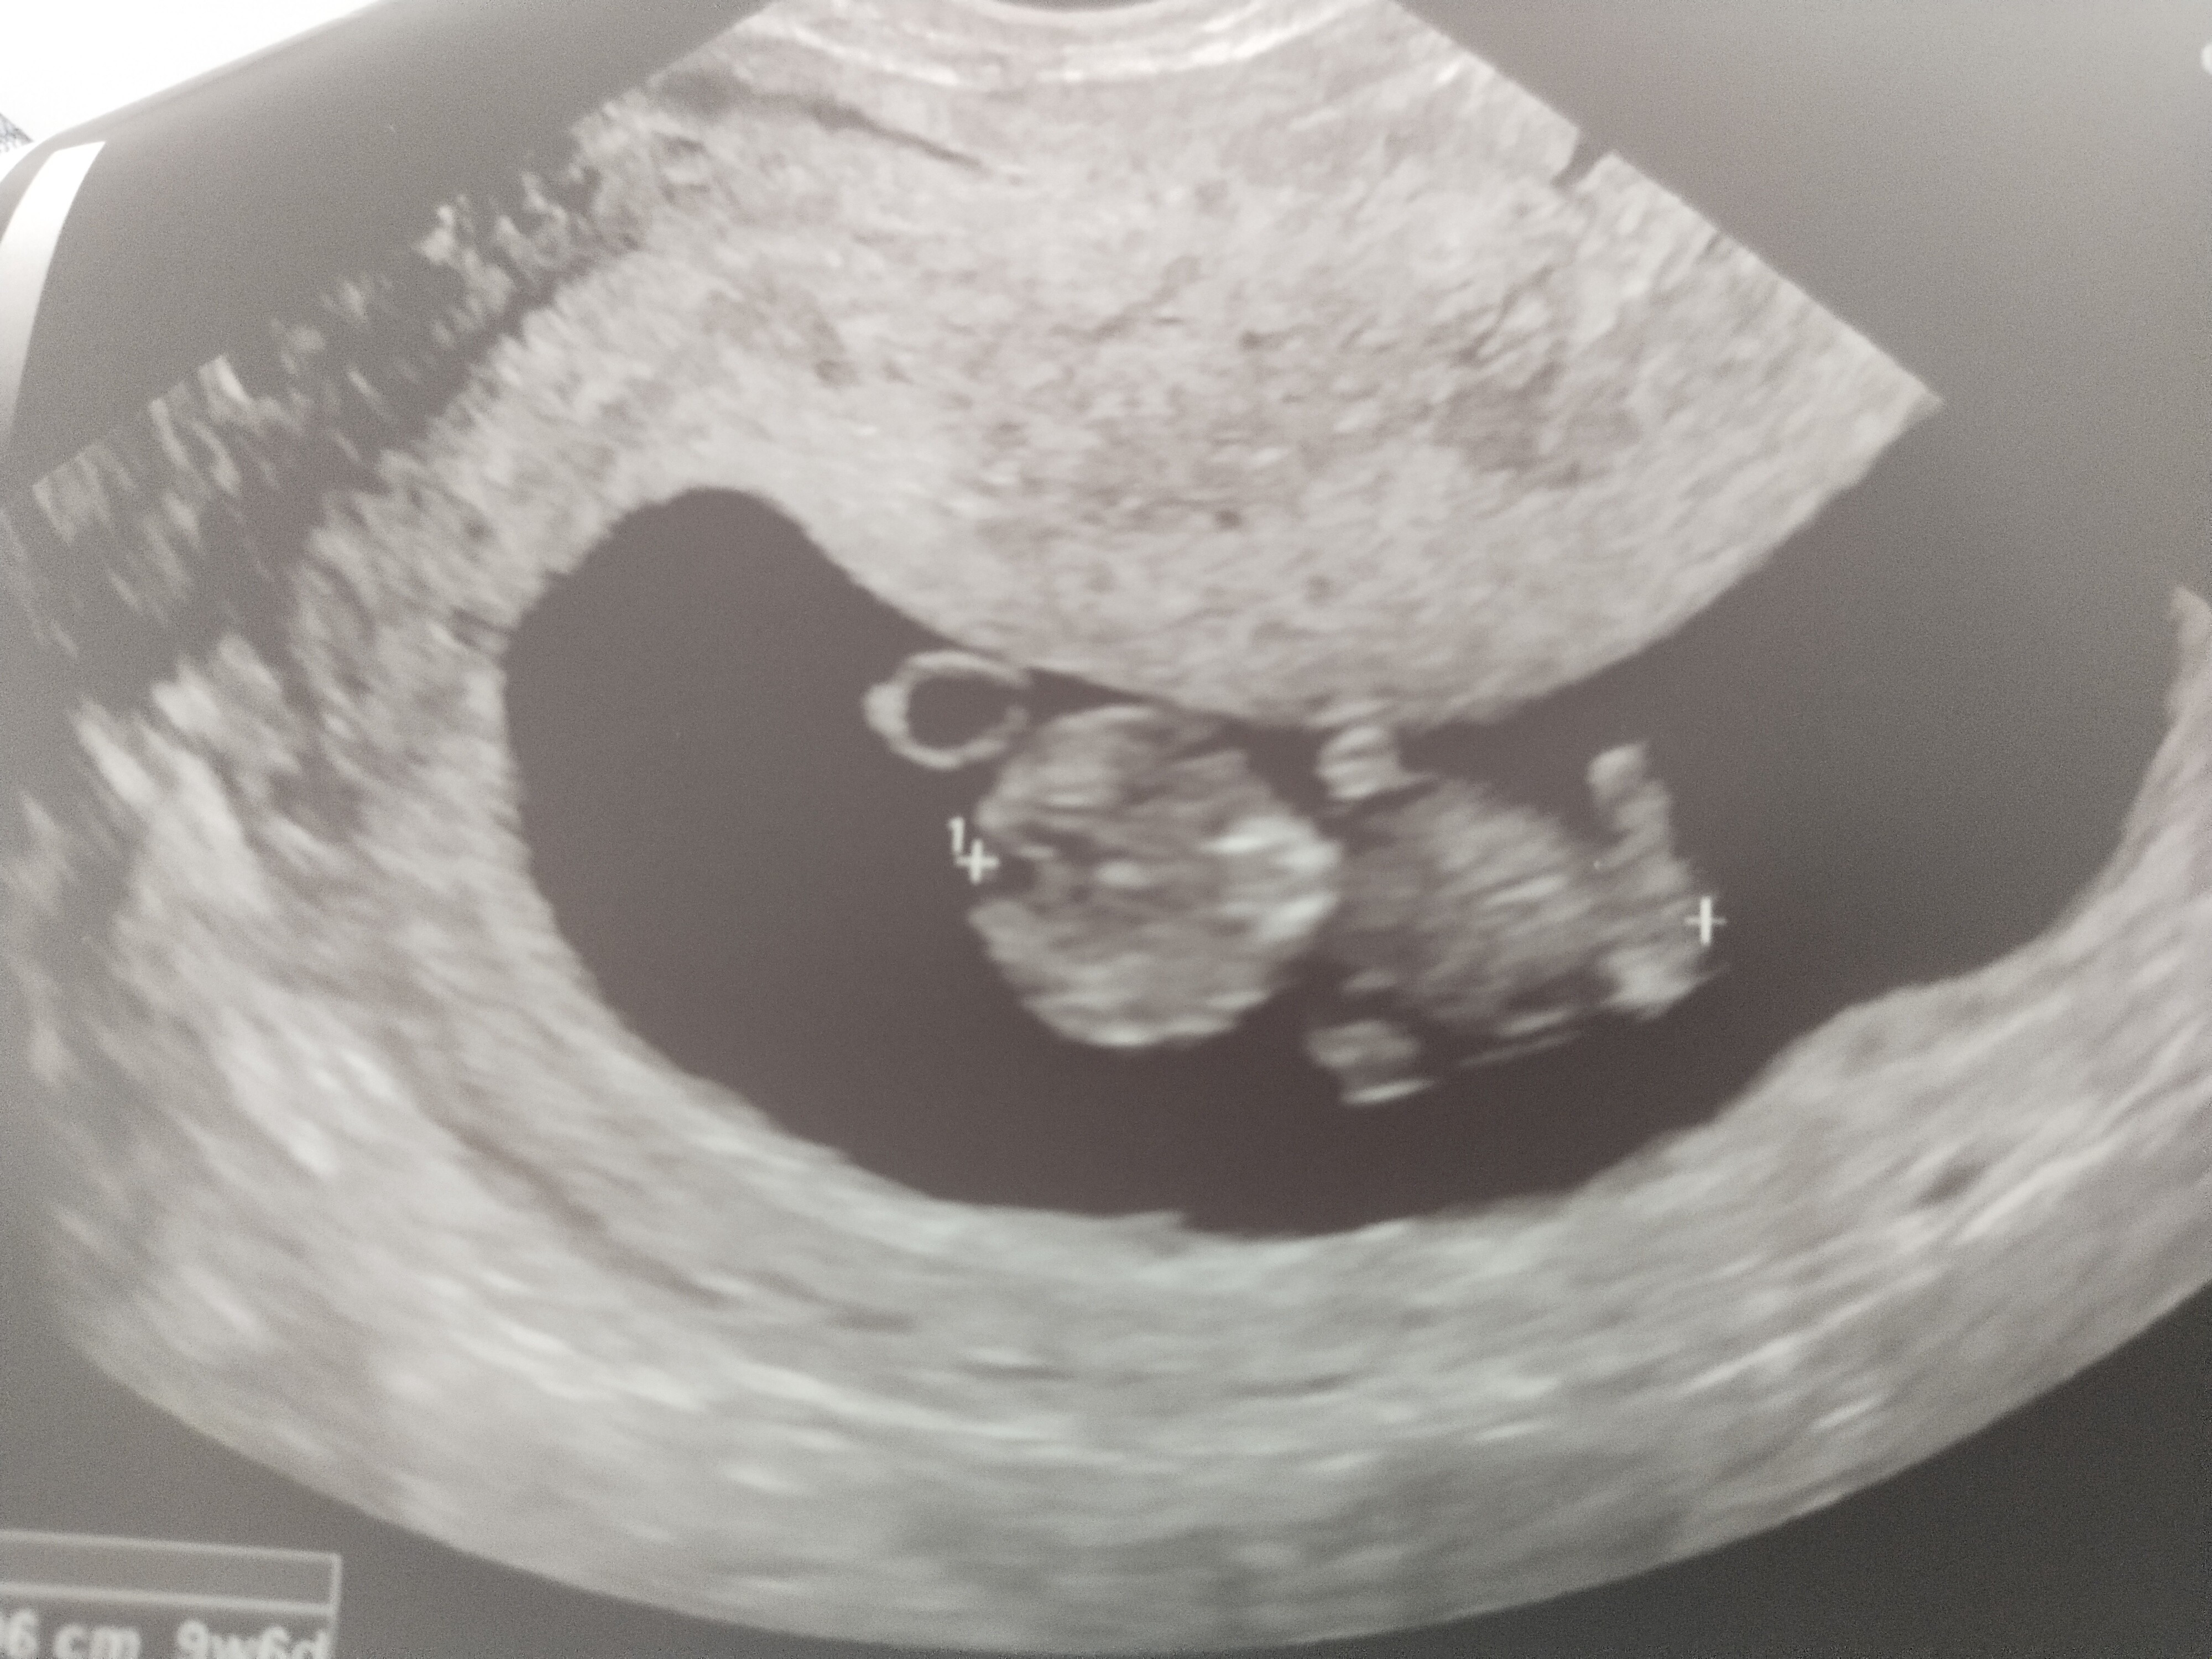

„Ciąża póki co zdrowa i rozwija się w odpowiednim tempie”.